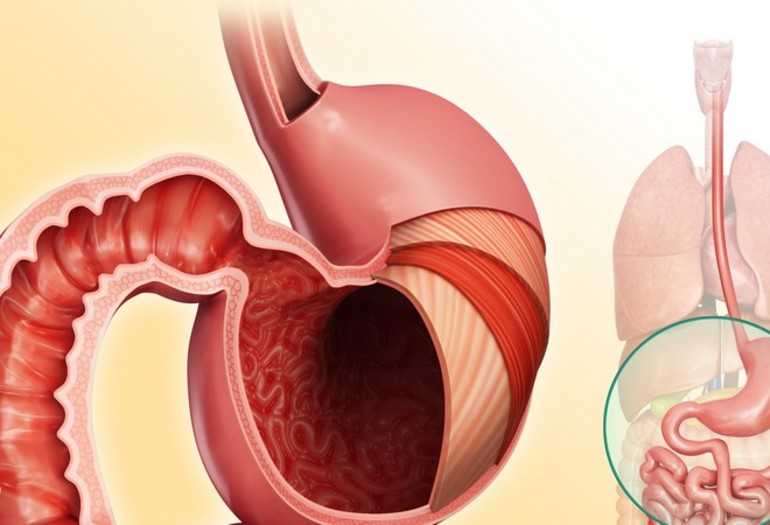

Информация и фотографии о хроническом гастрите и дуодените